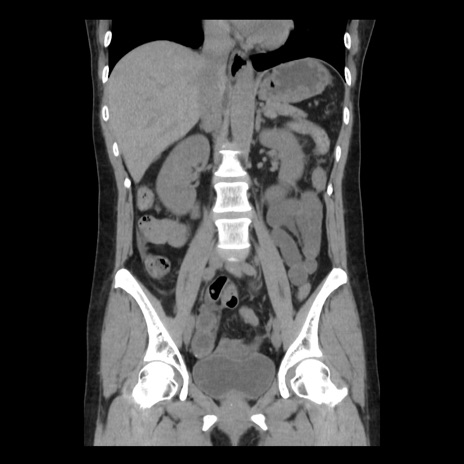

症例10(冠状断像)

【症例】 50歳代女性

【主訴】 腹痛

【現病歴】前日生レバーを食べた。今朝に排便あり。 昼前に突然発症の腹痛を生じ、当院救急外来を受診した。

【既往歴】 子宮筋腫にてで子宮全摘後

【身体所見】 意識清明、腹部:平坦、軟、下腹部やや左を中心に圧痛・反跳痛あり、筋性防御あり

【データ】WBC 7800、CRP 0.07